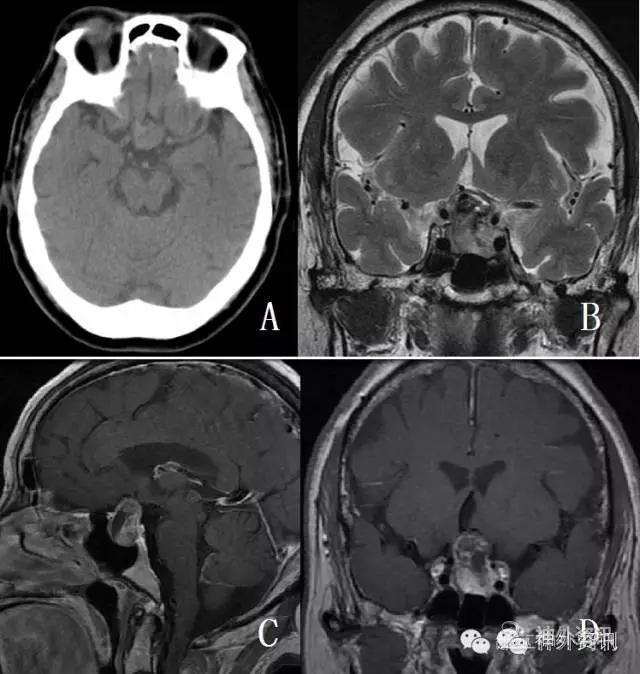

2月前患者睡眠时突发头痛,为前额部胀痛,程度剧烈,影响睡眠,伴恶心呕吐,呕吐物为胃内容物,无寒战发热,无意识障碍,无肢体抽搐。于当地医院就诊,查头颅CT提示垂体占位病变,因担心手术风险未治疗。此后头痛反复发作,2周前突发左眼失明,无眼痛,无恶心呕吐,来我院复查头颅CT及MRI,提示“垂体大腺瘤”(图1),要求手术收住入院。

图1. 头颅CT提示鞍区等密度病变,MRI显示T2像等低混杂信号,T1像强化明显,内有囊变,左侧部分侵袭海绵窦。